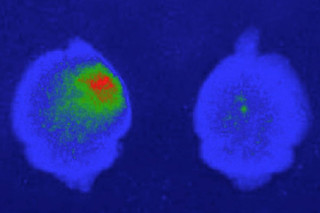

10亿分之一的CAQK肽(深蓝色)也靶向人类大脑样本中的损伤部位,显示出其精确药物递送的潜力。(图片来源:Mann 等人,2016 Nature Communications。经MacMillan Publishers Ltd. 许可转载)

Mann 等人,2016 Nature Communications。经MacMillan Publishers Ltd. 许可转载